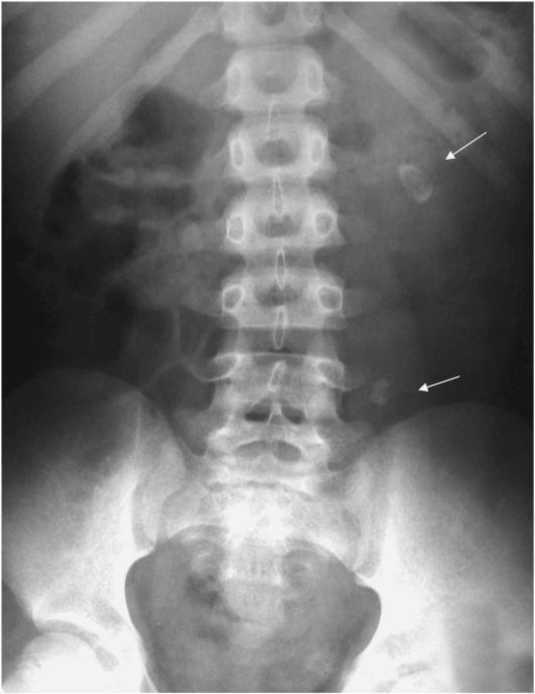

• урографию – рентгенологическое исследование почек и мочевыводящей системы после внутривенного введения контрастного вещества;